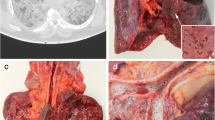

The lungs showed bilateral diffuse to global consolidation with a focus to the centrilobular areas. Reticular changes with peripheral accentuation can be found in both lungs.

Also, scattered ground glass opacities were found with a focus to the dorsal lung areas. In accordance, with resuscitation procedures, serial rib fractures were found. Additionally, general and coronary atherosclerosis to moderate degrees, cardiac hypertrophy, and minutely atrophic kidneys were detected.

A full autopsy has been performed. Examining the lungs, we found hyperaemic areas of more dense consistency with a particular focus on the centrilobular regions of both lungs and some subpleural hemorrhages (Fig. 1a–d). Minimal pleural effusions (right side: 50 ml, left side: 50 ml) and an intra-alveolar lung oedema accompanied the observed inflammatory processes (Fig. 2d, e). The latter resulted in a lung weight of 1500 g in total (right lung lobe: 855 g, left lung lobe: 645 g). Detailed histologic examination revealed inflammatory changes with a focus on the central areas of both lungs. More precisely, lymphocytic cell infiltration predominantly consisting of CD8 positive cells was found within the interstitial lung areas (Fig. 2e). Local aggregation of CD8 positive cells within the alveoli was found. Disseminated spots of activated type II pneumocytes were observed, and hyaline membranes and the presence of microthrombi within the lungs accompany the reported findings (Fig. 2a, c). Also, hemorrhagic alveolar infiltration was found (Fig. 2b), and mediastinal lymph nodes showed reactive hyperplasia. Concurring inflammatory changes in the lungs, morphological signs of systemic inflammation were found in terms of “septic spleen” and lipid depletion of the adrenal glands.

Macroscopic findings during the autopsy. An overview of the chest cavity (a) and more detailed pictures of the surface and cross-sections of the lungs (b–d) illustrating bilateral deep red hyperemic discolorations with peripheral hyper-inflation of the lungs. Exemplary deep venous thromboses of the femoral vein are illustrated (e)

Interestingly, we also found peripheral pulmonary embolisms (PE) involving the segmental (in the left pulmonary artery flow area) and sub-segmental vessels (in the right pulmonary artery flow area) in this case. The latter presented slightly ribbed without adhering to the vessel wall. Accordingly, deep vein thrombosis (DVT) in the leg veins was found without adherence of the thrombi to the vessel walls (Fig. 1e). The blood in the heart chambers and large vessels presented fluid.